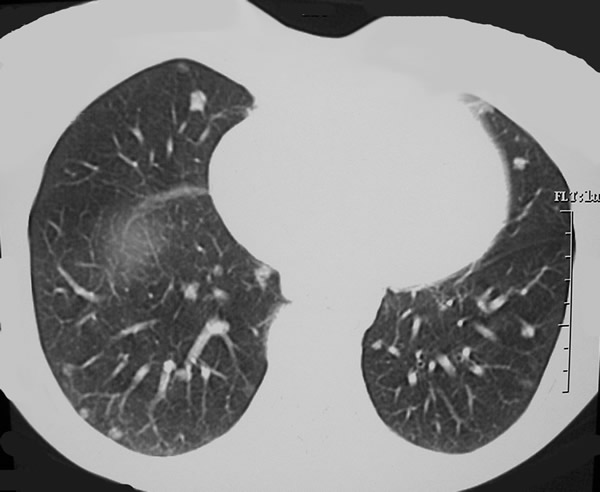

Figure 1. Chest CT showing multiple nodules in both lungs. Preoperative identification of the most suitable nodules to be resected by uniportal VATS is of paramount importance to the success of the procedure.

In the illustrative case (Figure 1), the target lesion is identified in the right middle lobe (Video 2 below). A roticulating endograsper is introduced parallel to the videothoracoscope with the port sleeve retracted along the stem and held in place by the same hand holding the scope. The roticulating arm of the grasper is displayed so that the grasper stem is confined at one corner of the incision while the grasping end of the arm is suspending the nodule cranially (Video 3 below). At this time, the assistant is holding the videothoracoscope by standing aside the surgeon. A roticulating endostapler is introduced with the roticulating edge already rotated upward with the thinner component on the right hand side. This is to facilitate the introduction of the endostapler in a narrow space by holding the stem of the instrument as a pen and gently sliding the endostapler, parallel to the videothoracoscope, as “a mediastinoscope under the pretracheal fascia”. The endostapler is inserted deeply into the chest in order to position the fulcrum inside the cavity thus allowing for jaws opening. At this point, the thinner anvil is immediately recognizable. At all times the insertion of the instruments inside the chest be should be observed using the thoracoscope. The surgeon holds both the endograsper and the stapler so that the stapler is positioned caudally to the lesion and the grasper gently positions the parenchyma between the jaws. At this point, the jaws are closed and the inclusion of the nodule in the specimen is visually confirmed. The endostapler is then fired, the jaws are opened, and the instrument is removed from the chest following the reverse sequence of movements that were used for the insertion. Multiple firings of the endostapler may be needed in order to fully detach the parenchyma from the lung (Video 4 below). Endoscissors can be also used to cut small bridges of tissues. Once the lesion is successfully wedge resected, an endobag, can be used to remove the specimen (Video 5 below). After hemostasis has been secured, a chest drain is inserted through the same port site.